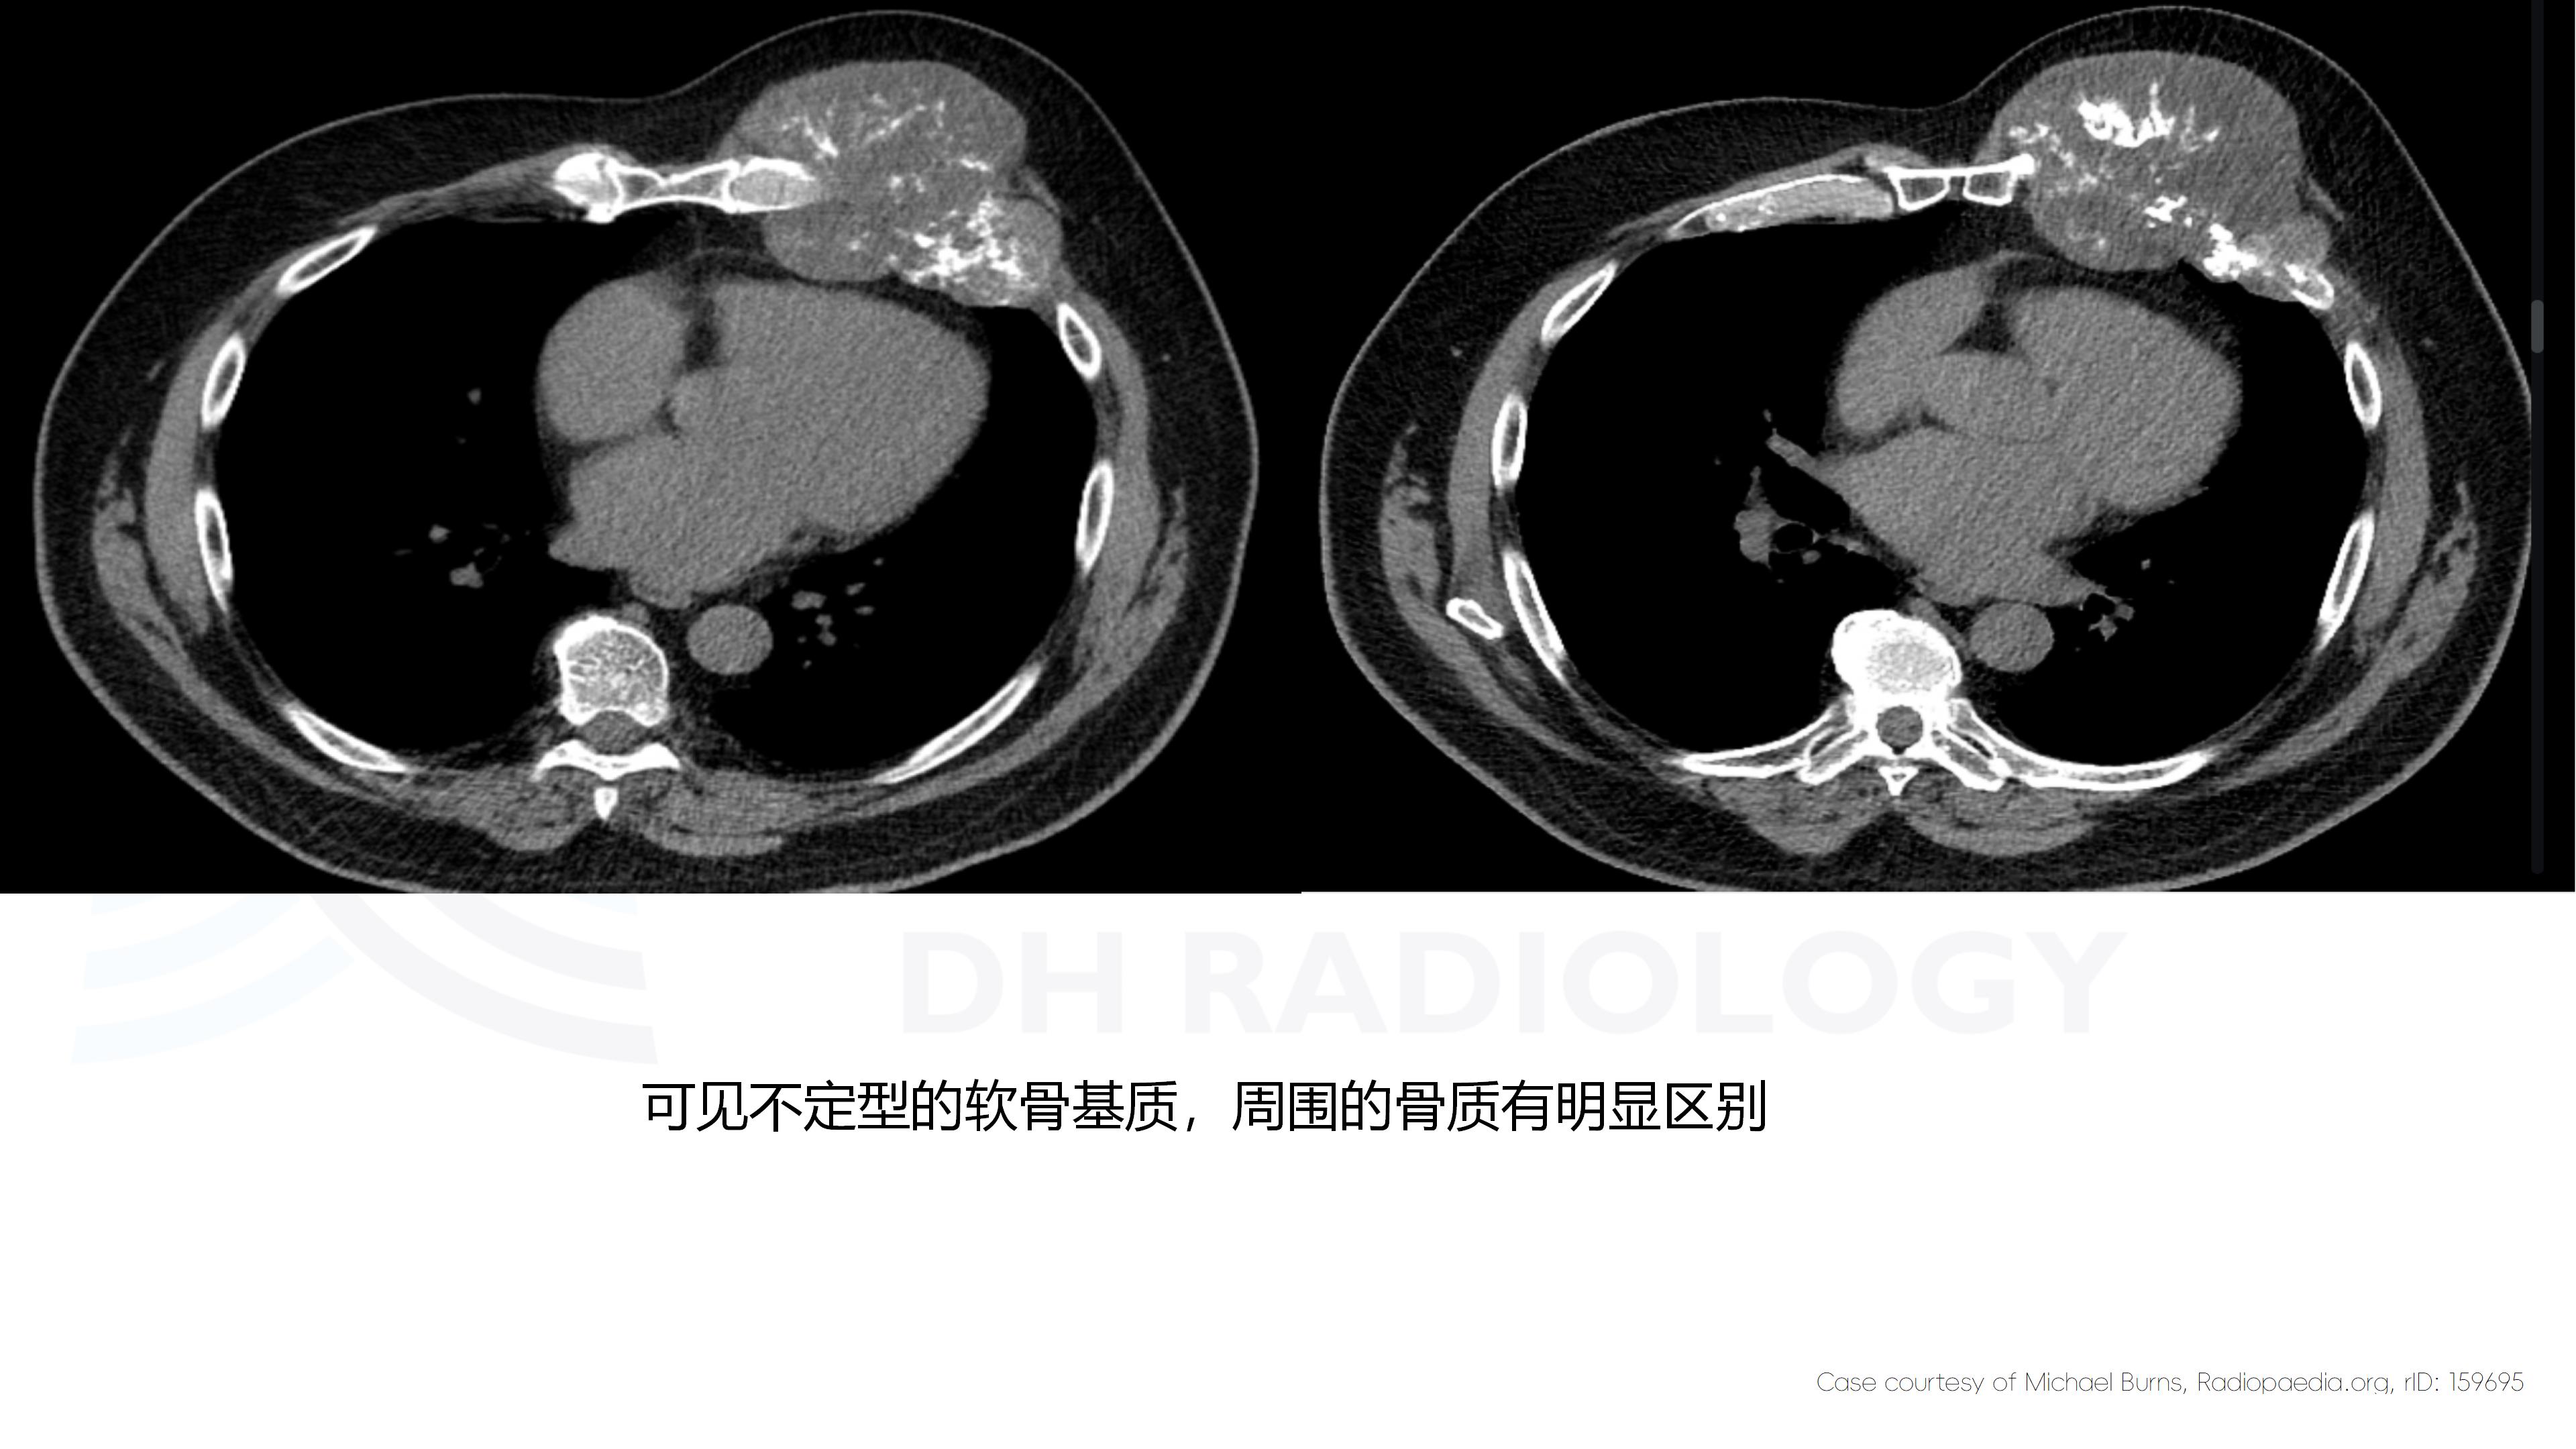

肋骨血管瘤

现病史:患者女,63岁,半年前活动后出现左侧胸痛,轻度胸闷,无咳嗽咳痰,无头痛头晕,无恶心呕吐,无腹痛等不适。温州大学第一附属医院就诊,未行治疗。半年来左侧胸壁隆起较前明显,活动后轻度胸痛症状,余无明显不适。